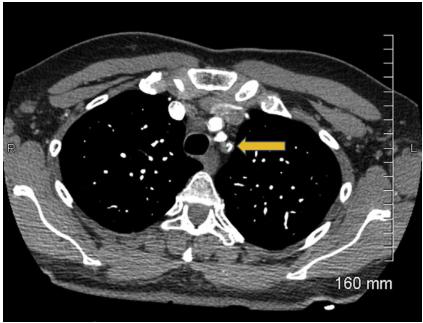

图1 入院心电图肌钙蛋白水平轻度升高,为0.7ng/ml,初步诊断为非ST段抬高型心肌梗死,遂予静脉输注普通肝素抗凝治疗。行胸部增强CT显示左锁骨下动脉近端血栓形成并延伸至主动脉弓(图2),并未看到左内乳动脉至左前降支移植物的图像。

图2 胸部增强CT图示胸部增强CT做完不久后,患者胸痛症状加重,并出现急性呼吸窘迫,需行气管插管和机械通气。